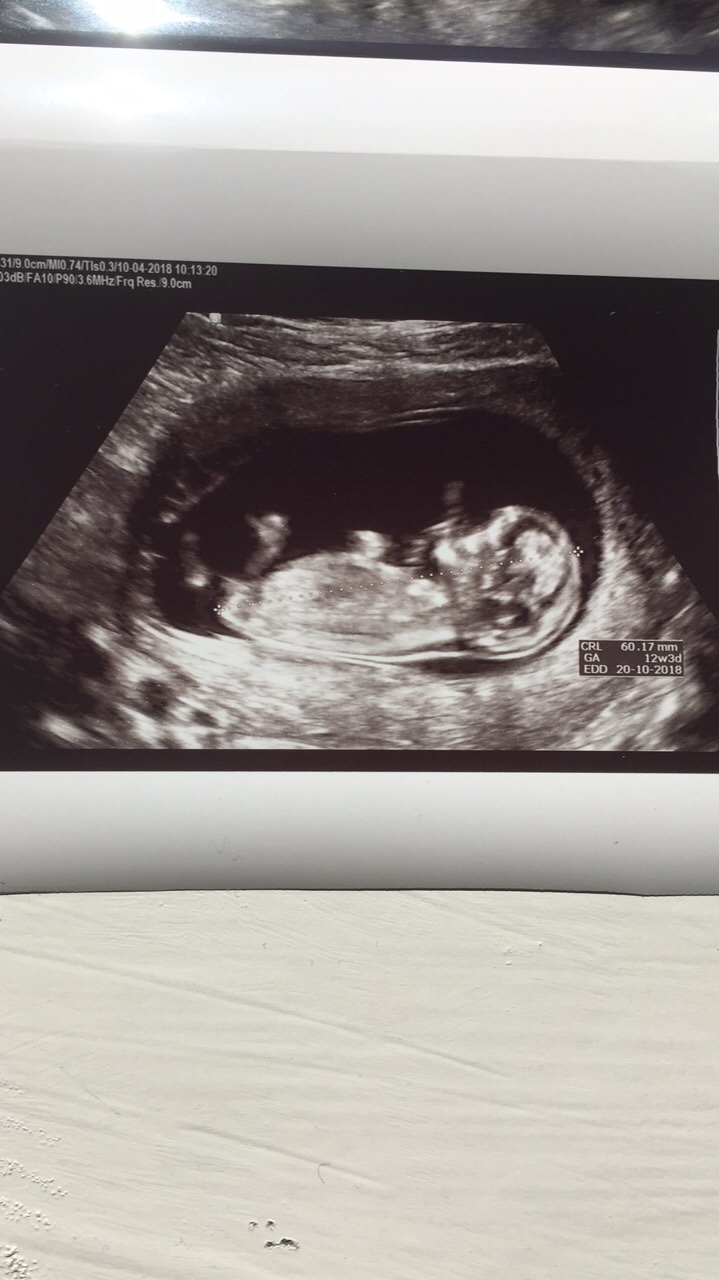

Jeg var på UL igår, 11+4! Ble målt til 12+3! En sprellende baby, som mest sannsynlig er ei lita tulle[emoji179][emoji179]

Veldig greit å bli satt frem! Blitt det både i uke 9 og igår! Men lar ivf-stå hvertfall til OUL![emoji5]Vanlig UL på sykehuset! Får så mange offentlige TUL jeg vil! Fordel med å bo i distriktet[emoji23][emoji23] jaa, hu sa at det så veldig feminint ut! Men kan jo selvfølgelig endre seg! Men jeg har hatt følelse på jente[emoji179][emoji179]